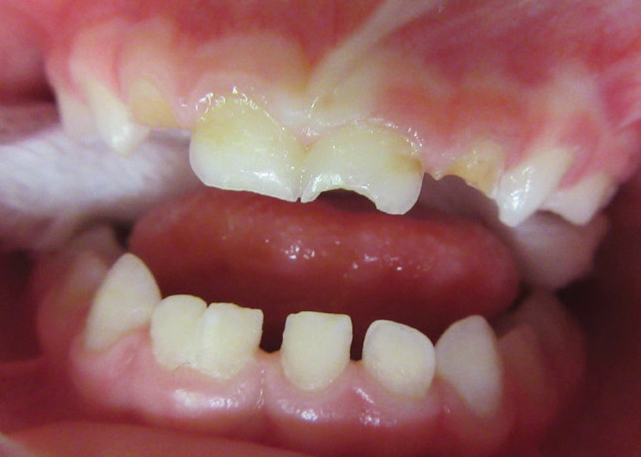

Patients with class-three malocclusions commonly present some of the most challenging cases we see. Often their occlusions also are complicated by deep underbites or crossbites leading to frequent fractures in restorative materials such as composite crowns when they are used as part of the treatment.

If you are treating a true skeletal class-three case, you will want to prepare the tooth mostly on the facial surface. This will allow the crown to seat far enough lingually for it to clear the lower incisors when the child bites into maximum intercuspation.

If, however, the patient has a mildly trapped dental class-thee occlusion and you feel you might be able to correct the situation by crowning the anterior incisors, you will want to prepare the tooth mostly from the lingual side. This will allow you to flair the crown labially when seating. Often it proves helpful to adjust the incisal edges of the lower incisors, in many cases thus allowing for the anterior upper and lower teeth to meet end to end.